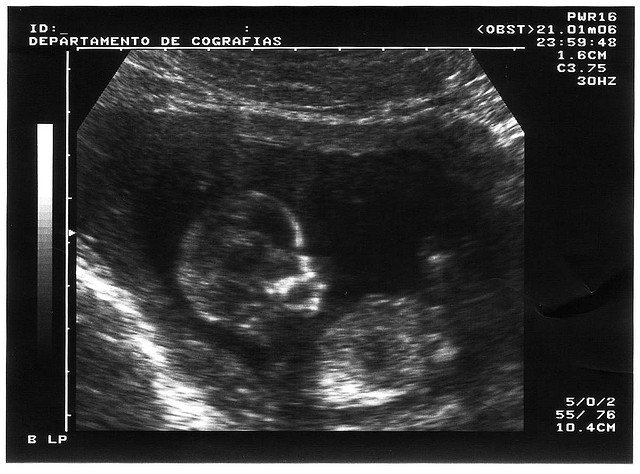

Resulta que un 5% de los fetos tiene personalidad en las redes sociales y el 7% tiene una dirección de correo electrónico. Los padres lo hacen para compartir la información con la familia y los amigos sobre el embarazo, la alegría por el próximo nacimiento, el orgullo y la pasión del momento.